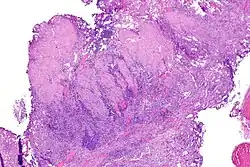

Inwazja warstwy mięśniowej raka urotelialnego

Kluczowym elementem wpływającym na rokowanie jest głębokość nacieku nowotworowego. Początkowo inwazja blaszki mięśniowej właściwej może przebiegać jako obecność pojedynczych komórek, klastry lub gniazda komórek w górnych warstwach blaszki mięśniowej właściwej, zwykle skojarzonej z infiltracją komórek zapalnych[79]. W późniejszych etapach inwazji obecne są klastry lub rozlane arkusze komórek nowotworowych w obrębie blaszki mięśniowej właściwej[79].